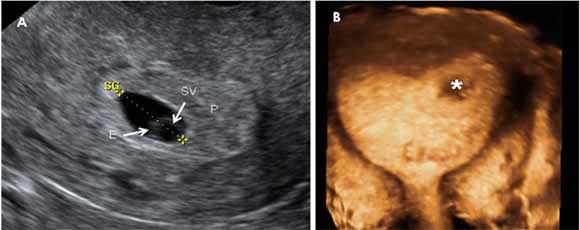

En la ecografía precoz ya puede verse el embrión en forma de punto blanco y en su interior el corazón latiendo. Los más modernos aparatos de ultrasonidos también permiten además de ver en colores el corazón, escuchar su latido. Lo idóneo es realizar esta ecografía por vía vaginal, ya que por vía abdominal es aún pronto para visualizar el embrión.

- El embrión ya mide entre 2 y 4 milímetros en la semana 6 de embarazo.

- Esta medida es la longitud desde la cabeza (el polo cefálico) hasta el final de la columna vertebral (el polo caudal). Por eso a esta medida se le llama LCC en español (longitud cráneocaudal) o bien LCN longitud cráneo nalga o CRL en inglés ("crown-to-rump length"). Es la más utilizada para medir al embrión, obviando la distancia hasta los pies, ya que las piernas generalmente están dobladas y sesgan la longitud real del bebé.

- El corazón ya está latiendo, signo que se puede apreciar mediante ecografía. Es un corazón muy pequeño que late muy deprisa, entre 120 y 160 latidos por minuto